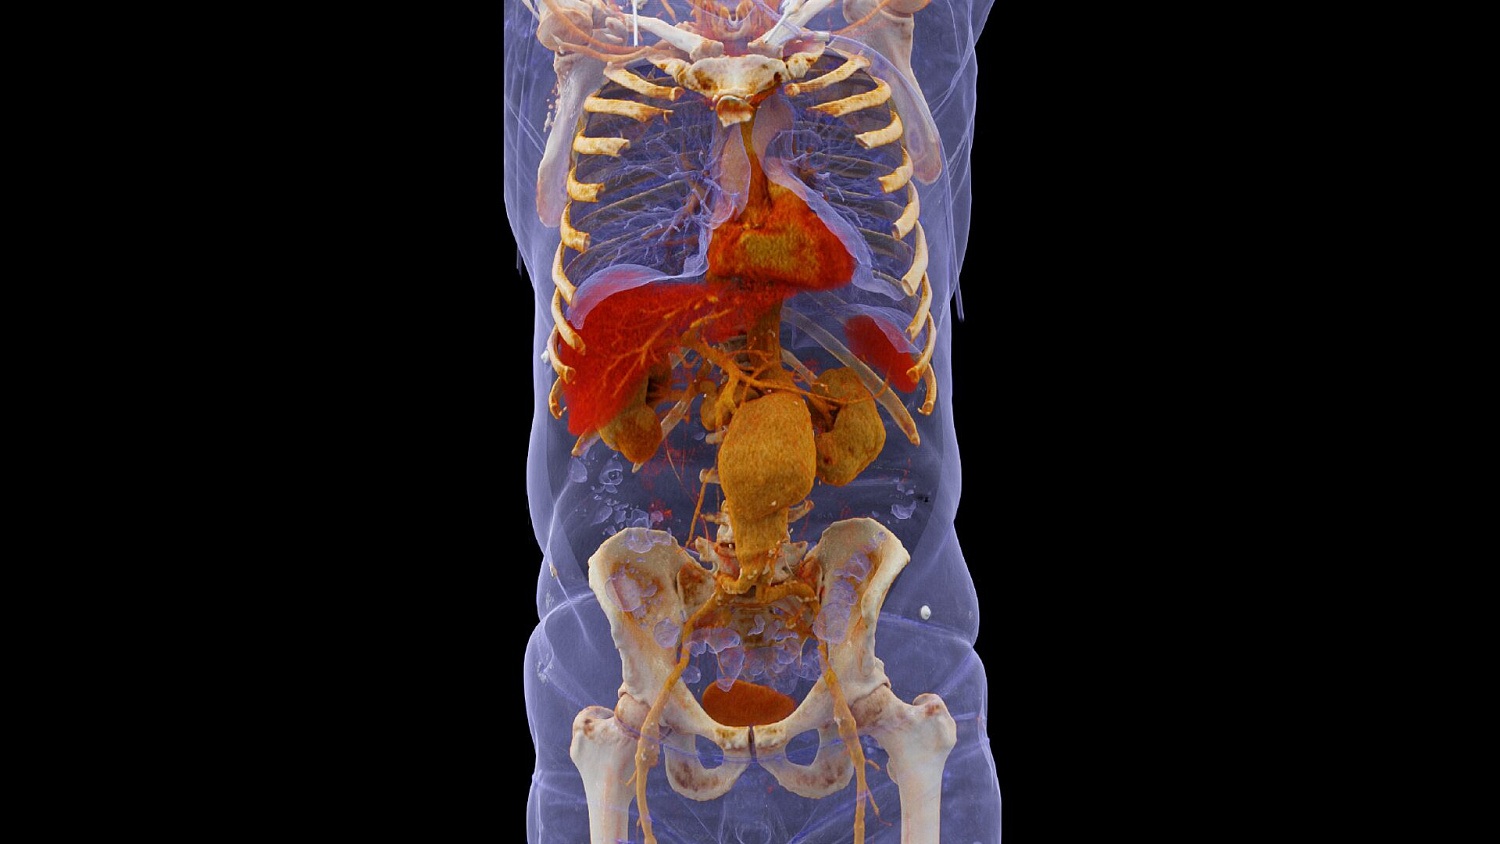

Шаг 1. 4D-визуализация при сниженной вдвое дозе облучения

Несмотря на явные преимущества динамических исследований, применяемая в них доза излучения служит существенным препятствием для более широкого распространения этих методов, особенно для оценки перфузии внутренних органов. SOMATOM Force позволяет существенно снизить барьер лучевой нагрузки не только за счет расширения охвата до 22 см в перфузионных исследованиях (и до 80 см при КТА), но и путем снижения дозы облучения на величину до 50% по сравнению с тем уровнем, который характерен для ведущих КТ-систем. Теперь перфузионные исследования, например печени, можно проводить с дозой облучения сравнимой с дозой обычных многофазных исследований.